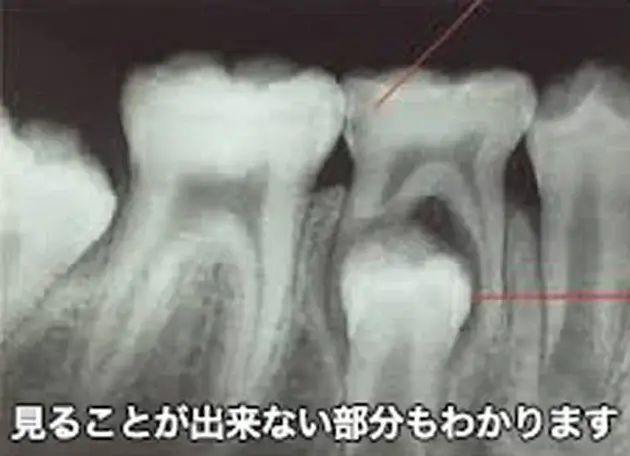

バンドという装置が奥歯につくとレントゲン写真でむし歯の大きさを確認するのが難しくなります。

当院にはレーザーの光を歯にあてて、むし歯が拡大しているかを確認する装置※があります。

バンドを外さなくても虫歯の大きさをチェックでき、痛みを感じることなくむし歯の大きさを知ることが出来ます。

※光学式う蝕検出装置(ダイアグノデント)認証番号:21200BZY00321000